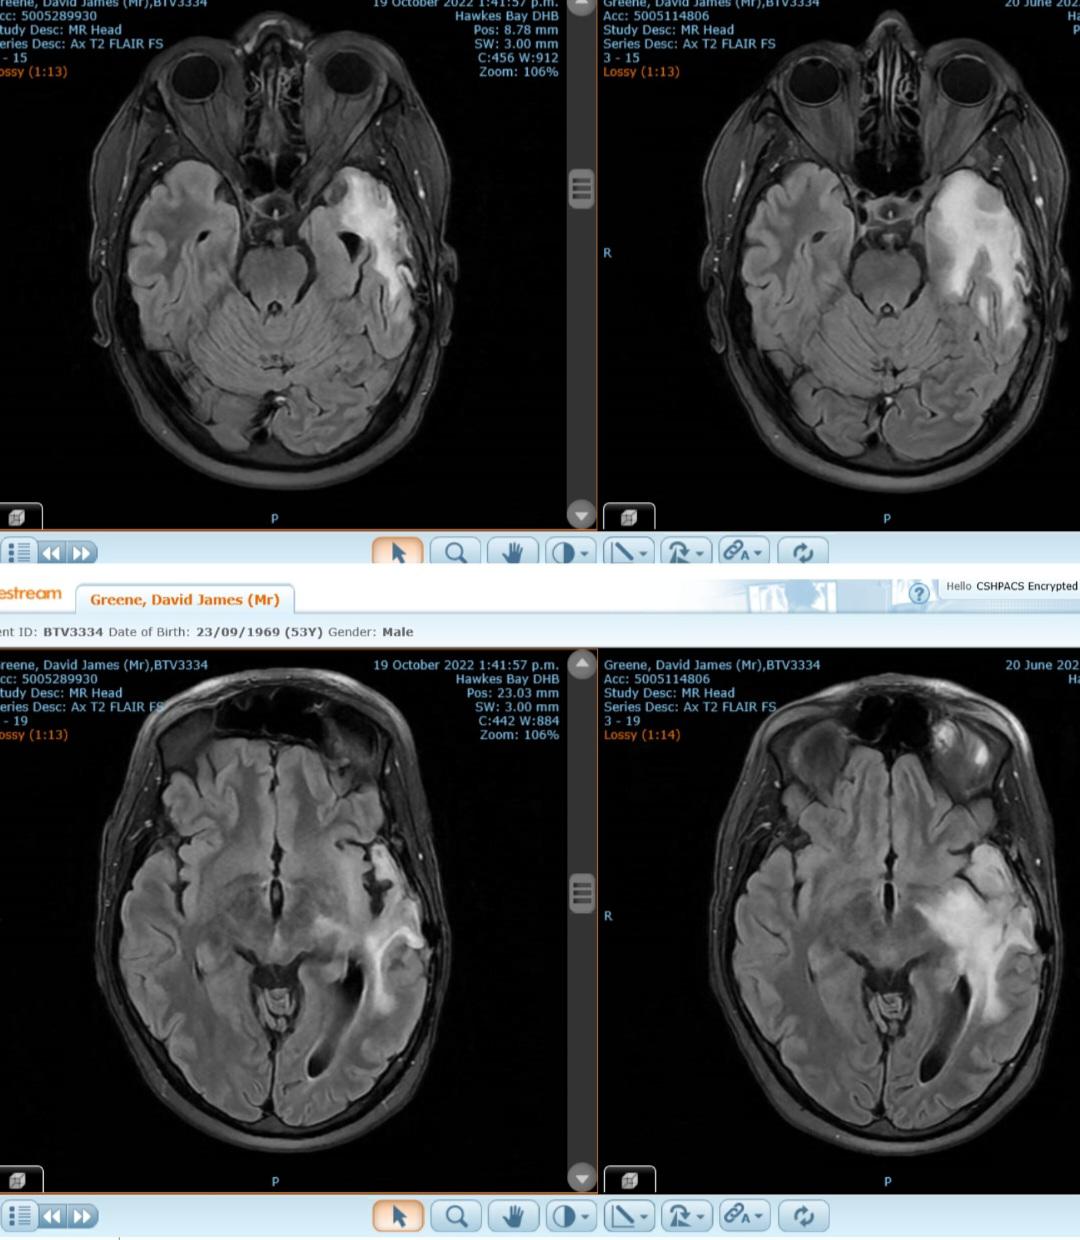

Main image

After David's MRI on October, having had 2 of the initial 6 cycles, we were absolutely stunned to see such a change in the size of David's tumor.

The images on the right side show the tumor (the white area) as it was in June 2022. The images on the left, show the tumor (the considerably smaller white area) in October 2022.